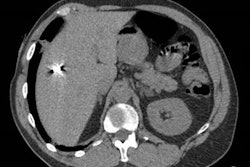

In this session, photon-counting CT (PCCT)'s potential in breast imaging will be discussed, with research suggesting it has similar image quality to dedicated breast CT.Stefan Sawall, PhD, from the German Cancer Research Center in Heidelberg will discuss findings on PCCT as a newcomer in breast screening. Sawall and colleagues used breast and thorax phantoms to represent realistic patient positioning. PCCT dose levels varied between 7 mGy and 25 mGy (CT dose index volume [CTDIvol]) at 120 kV in ultrahigh resolution mode. Meanwhile, images for dedicated CT were obtained using a standard protocol with a dose of 7 mGy (CTDIvol) at 49 kV.

The researchers wanted to compare the two methods by evaluating contrast-to-noise ratio of masses, the noise power spectrum, and the structural visibility of fibers and calcifications. They found that the contrast-to-noise ratio between masses and background was 1.3 on average when only using the breast phantom. Including the thorax phantom though, these differences varied between 0.9 to 2.3 mGy.

The researchers also found that the noise power spectrum's peak frequency in PCCT was 0.45 mm-1 compared with 0.40 mm-1 in dedicated breast CT. Additionally, calcifications down to a size of 0.29 mm and fibers down to a size of 0.23 mm could be identified in both systems' respective images.

Sawall et al suggested that PCCT could become an alternative to dedicated breast CT by providing additional information, such as identification of sentinel lymph nodes. They called for more studies on dosage delivered to other organs.